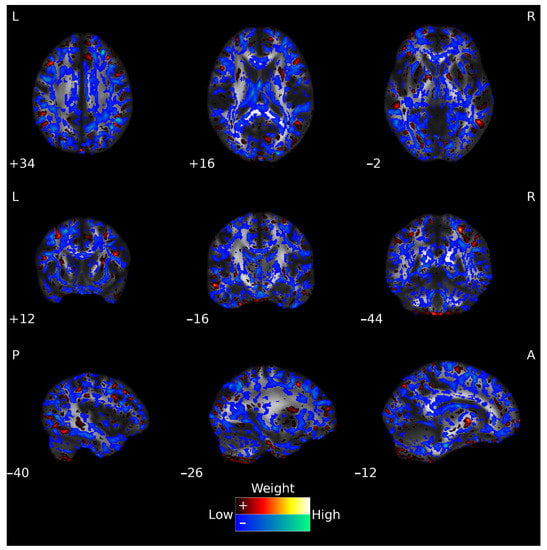

3.2. GM Classification

3.3. FA Classification